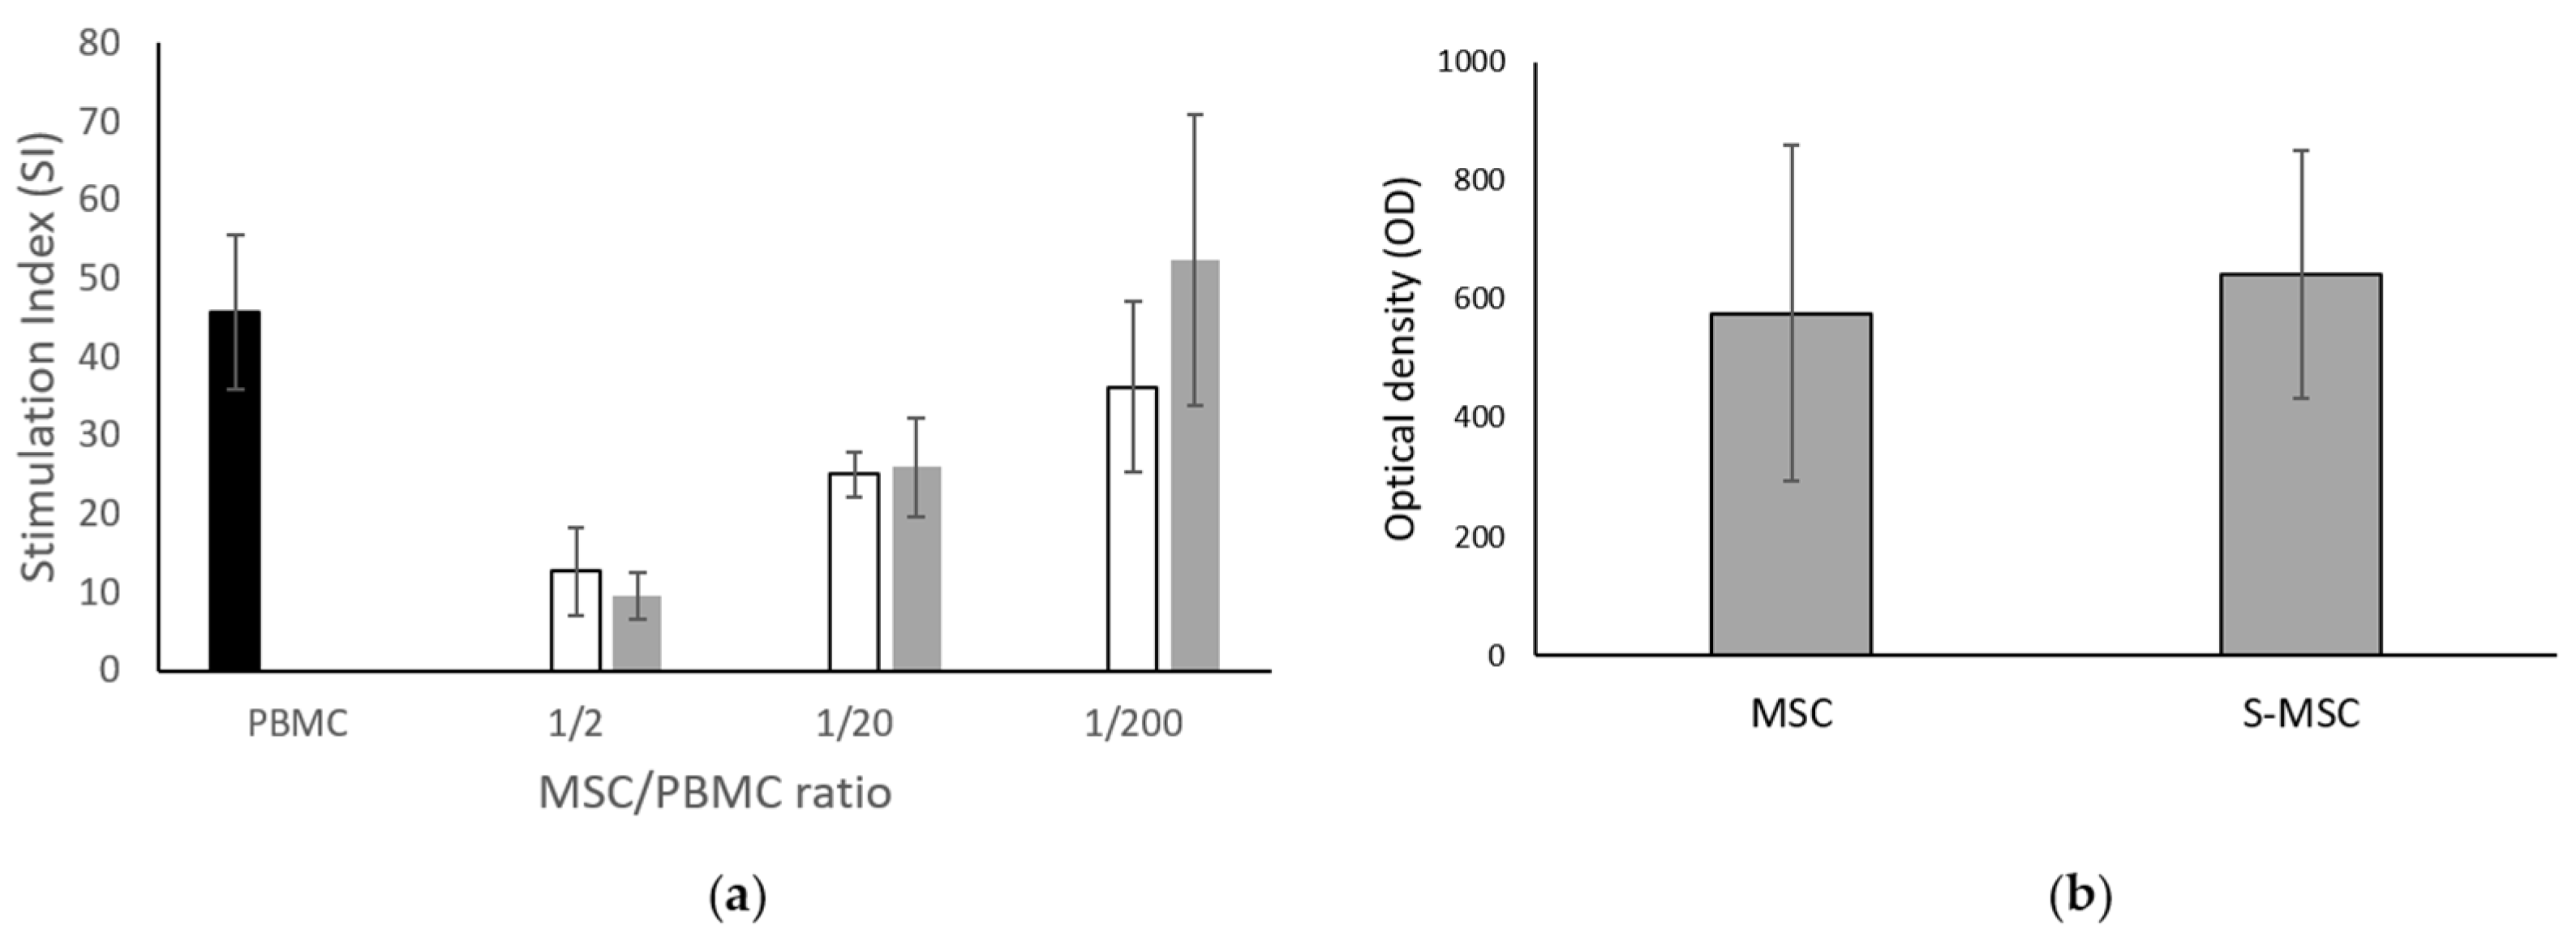

2.2.4. MSC Immunomodulation Capacity

2.2.5. MSC Metabolic Activity

3.1. MSC and S-MSC Characterization